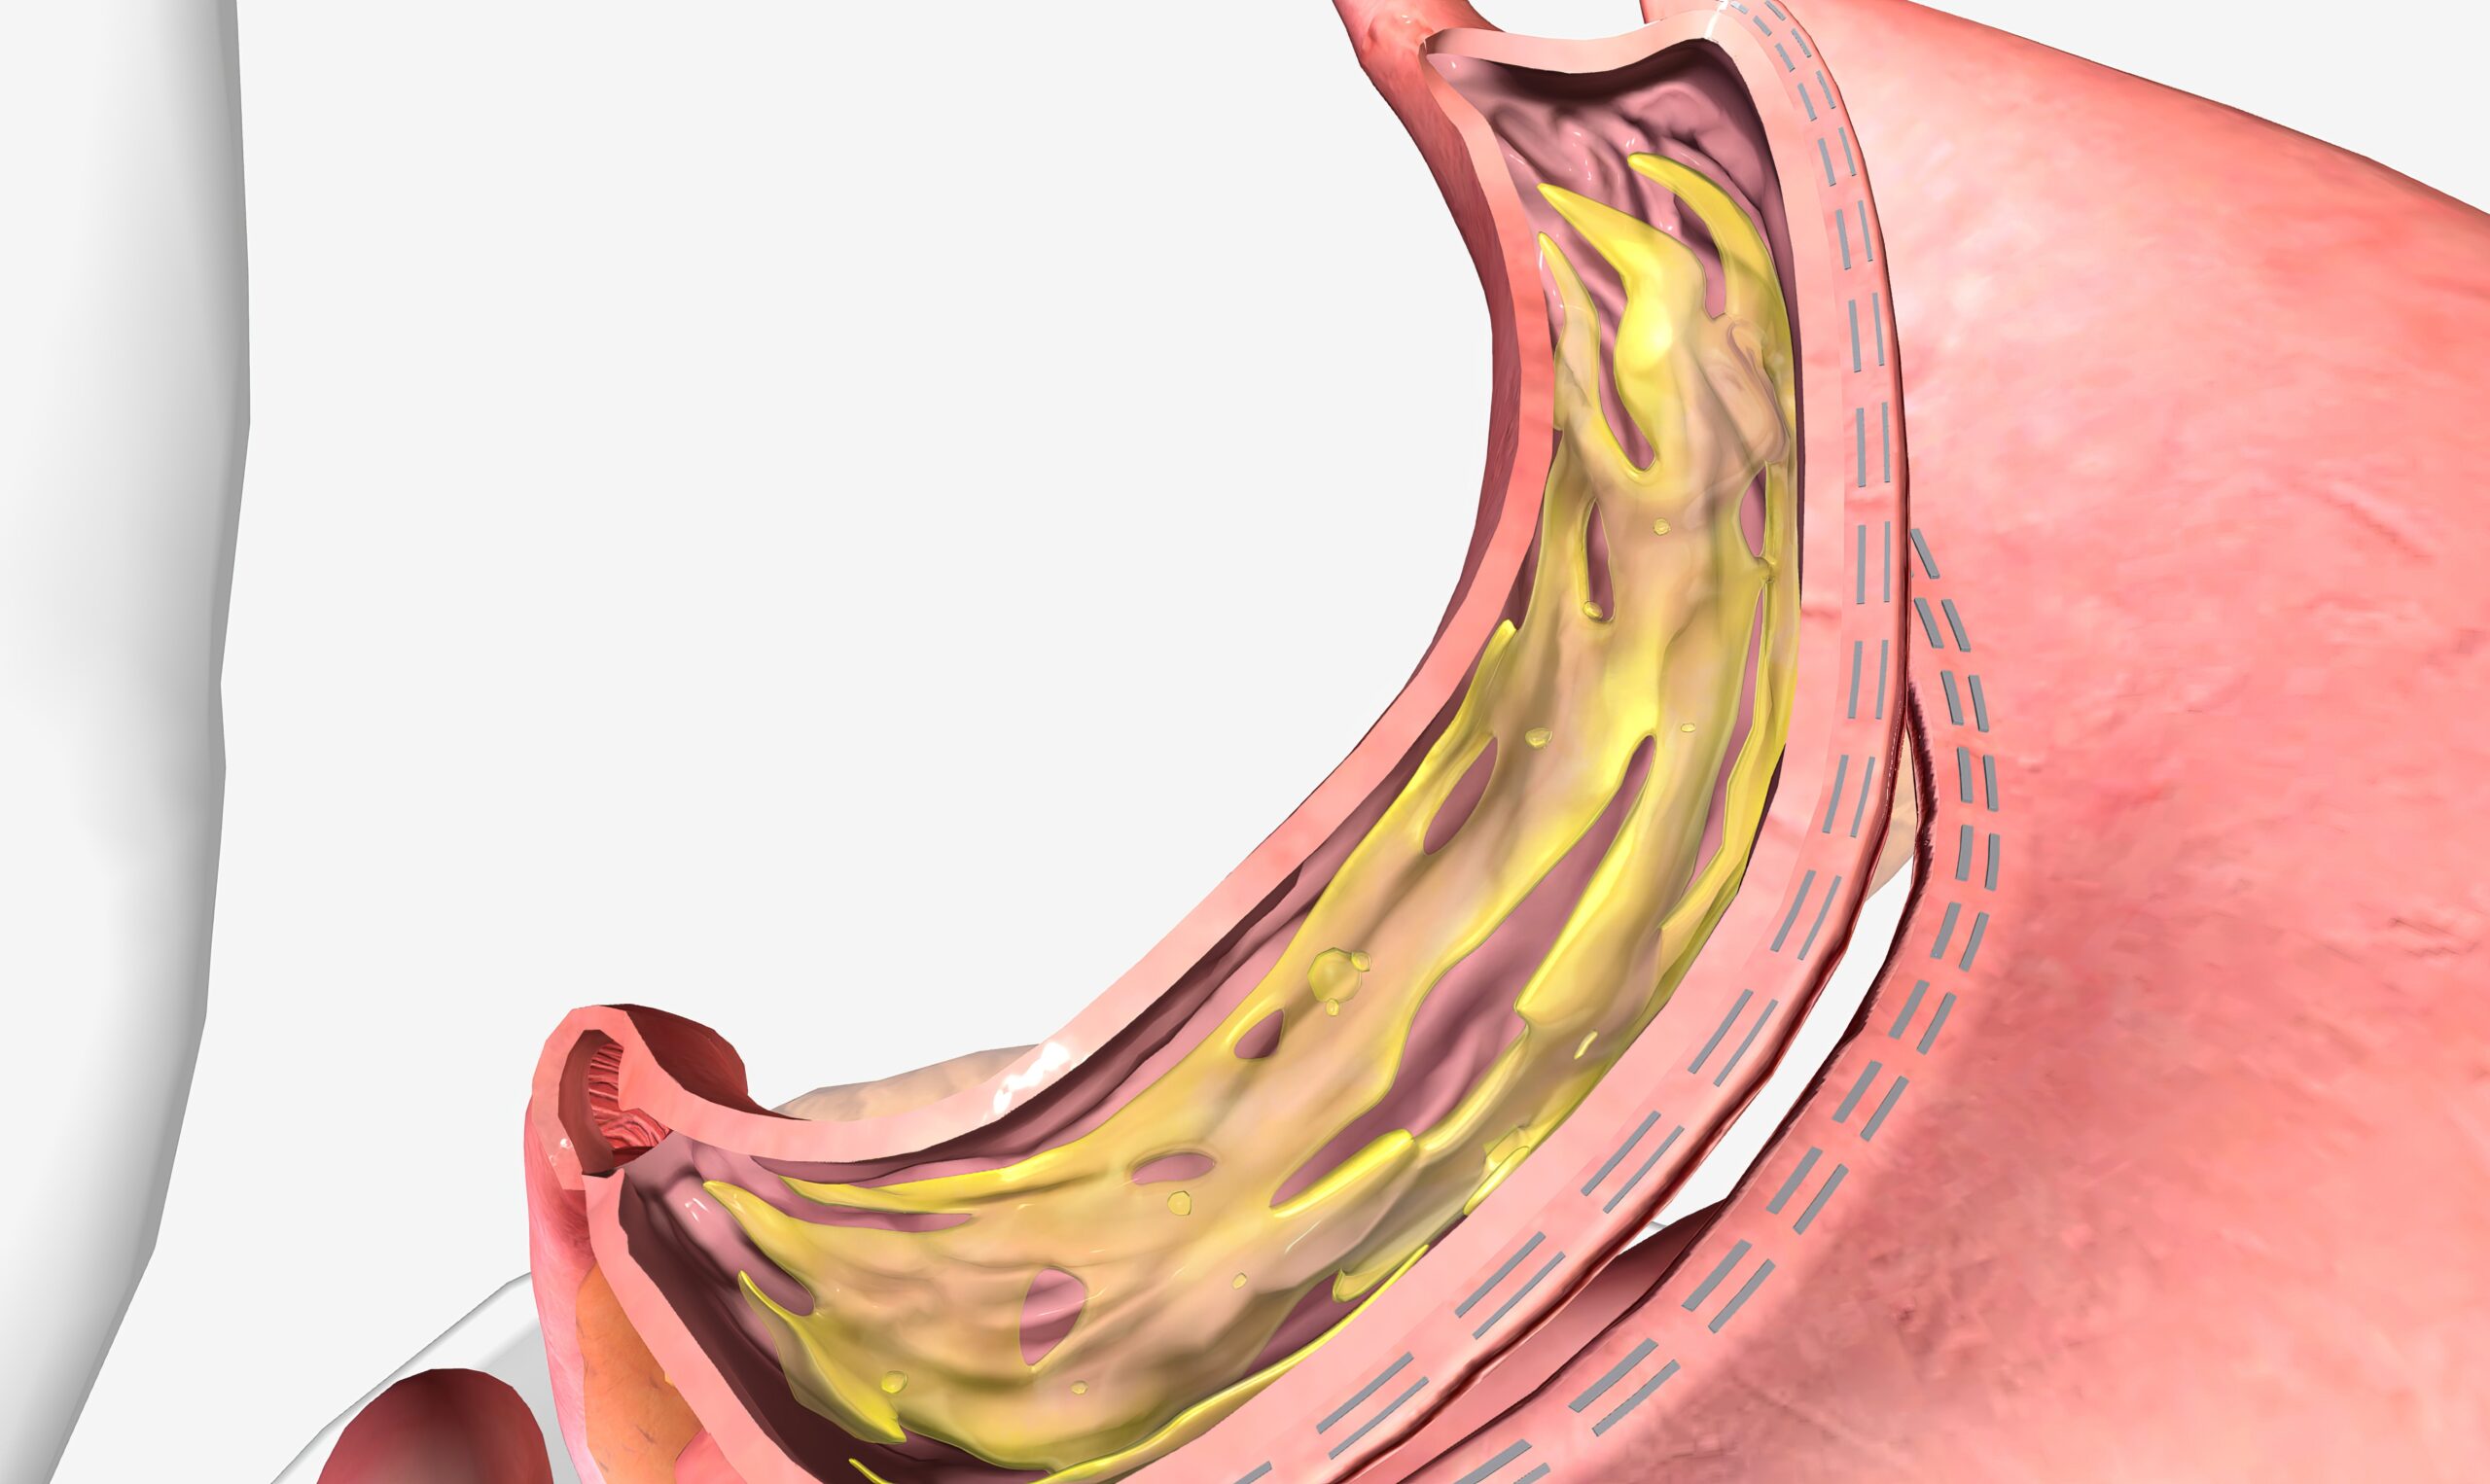

切胃手术,也称为胃袖状切除术,是一种减肥手术,通过切除大约75%的胃部来限制食物摄入量,从而帮助减重。这种手术不仅减小了胃的大小,还可能影响到与饥饿和饱腹感相关的激素,帮助人们更长时间地感到饱腹。切胃手术对于改善或解决与肥胖相关的多种健康问题,如糖尿病、高血压等,都有显著效果。